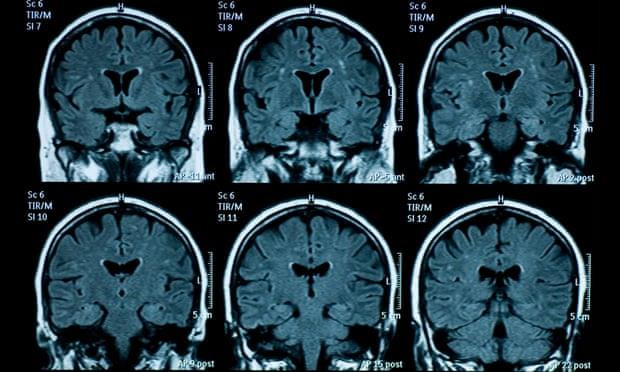

Cụ thể, so với trước đại dịch, nhóm thanh thiếu niên ở giai đoạn hậu phong tỏa có vỏ não mỏng đi và sự phát triển của vùng hồi hải mã và hạch hạnh nhân lớn hơn. Điều này cho thấy các quá trình phát triển não đã tăng tốc. Nói cách khác, bộ não của họ đã già đi nhanh hơn.

Sự khác biệt về tuổi của não bộ là khoảng 3 năm. Ảnh: Getty Images

Ông Ian Gotlib - Giáo sư tâm lý học tại Đại học Stanford, trưởng nhóm nghiên cứu - cho biết: “Sự khác biệt về tuổi tác của não bộ là khoảng 3 năm. Chúng tôi không nghĩ rằng não bộ phát triển nhanh chóng như vậy, do lệnh phong tỏa chỉ kéo dài chưa đầy một năm”.